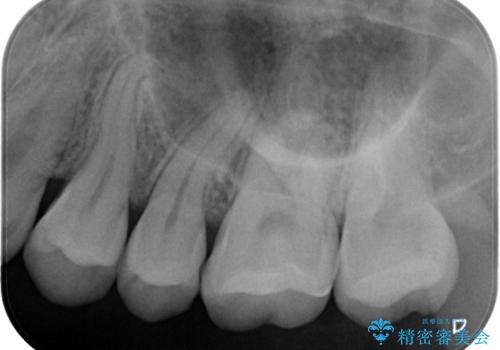

- 奥歯の銀歯が目立つということで来院されました。もともと入っていた銀歯を取り、虫歯の治療を行い、型取りを行ないます。

よく銀歯の下が虫歯になっていることがあります。

今回の患者様も銀歯を取ってみたら大きな虫歯になっていました。

虫歯をとり、銀歯から白いセラミックになったためかなり喜んでいただきました。